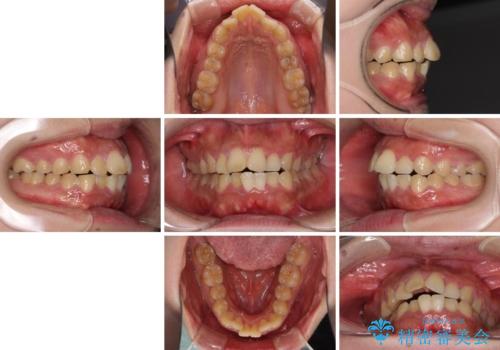

- 20代女性

- 審美装置

- 1年11ヶ月

- 口元の突出感と上下前歯のでこぼこを気にして来院された患者様です。

上下前歯部叢生のスペース獲得のため、上下顎左右小臼歯各1歯(計4本)を抜歯して、矯正治療を行うこととしました。

口腔内の清掃性に問題があり、虫歯のリスクが極めて高かったため、短期で治療を終えることを最優先に治療を進めました。